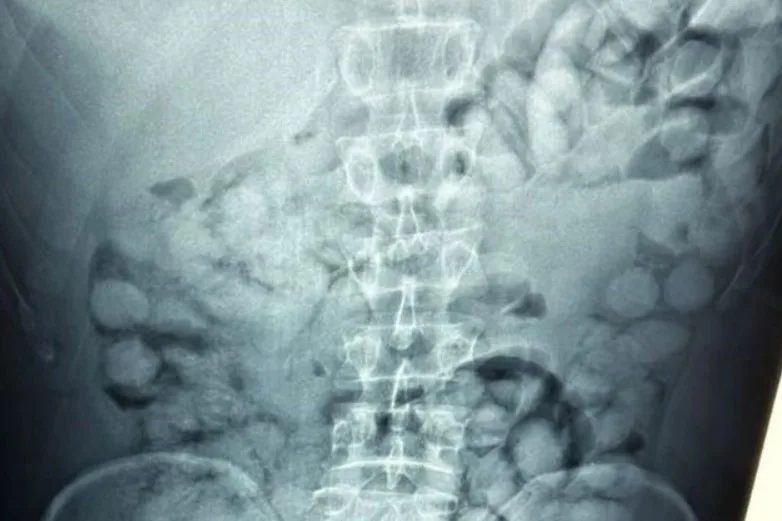

Στα χέρια των ανδρών της Δίωξης Ναρκωτικών έπεσε στο αεροδρόμιο «Ελ. Βενιζέλος» ένας Βραζιλιάνος, ο οποίος σε σχετικό έλεγχο που του έγινε και στη συνέχεια σε ακτινογραφία, άφησε άφωνους ακόμα και τους αστυνομικούς, από την ποσότητα ναρκωτικών που είχε καταπιεί σε 100 αυτοσχέδια «αυγά» των 11 γραμμαρίων το καθένα, με σκοπό την μεταφορά καθαρής κοκαΐνης από την Λατινική Αμερική στην Ελλάδα.

Στην ακτινογραφία που έδωσαν οι Αρχές στην δημοσιότητα, διακρίνεται ξεκάθαρα ότι όλο το στομάχι του και το έντερό του είναι γεμάτο από αυτές τις συσκευασίες με συνολική ποσότητα πάνω από ένα κιλό καθαρής κοκαΐνης.